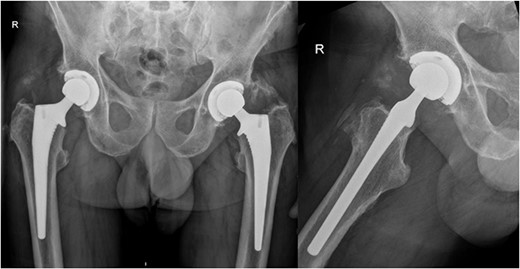

On examination, he had an antalgic gait and his range of motion was globally restricted due to pain. There was significant swelling and erythema over the operative site. His blood investigations demonstrated that his inflammatory markers were mildly elevated: white cell count (WCC) 8.5, CRP 14. X-rays showed satisfactory position of the implants (Fig. 2).

AP pelvis and lateral right hip radiographs 6 weeks post primary right THR when our patient presented with clinical signs of PJI. The implants were in a satisfactory position.